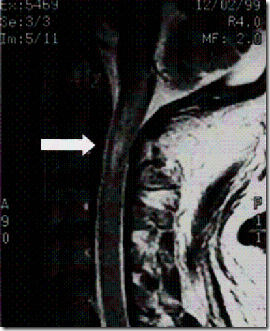

RMN realizada 10 meses más tarde mostrando un cordón medular atrofiado ( Morandi)

Otro ejemplo de este tipo de mielopatías postmanipulativas lo describió Chung (16). Se trataba de un varón de 46 años, con antecedentes de parálisis del VI par craneal y neuritis retrobulbar, que tras recibir una manipulación cervical por parte de un bonesetter chino sufrió una tetraplejia súbita con dificultades respiratorias. La RMN cervical practicada de urgencia reveló un edema medular C1-C2, con ausencia de alteraciones articulares y discales. Tras el tratamiento farmacológico, a los 5 días el paciente volvió a caminar. La mejoría fue progresiva hasta la aparición, 8 meses después de la manipulación, de una diplopia súbita. La RMN practicada en esta ocasión reveló que el edema cervical había evolucionado a una siringomielia cervical.